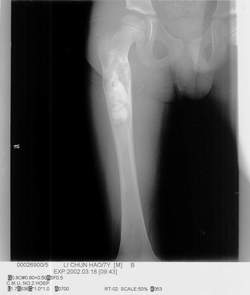

骨囊腫(UBC),又叫單純骨囊腫,其病變腔內充填為液體,四壁為薄的殼膜。單純性骨囊腫常發生於5到15歲的兒童,男性發病多於女性,比率約為2:1。病變部位多在長骨的乾骺端。最常見部位為肱骨近端,其次為股骨近端。活動性(active相對具有侵襲性的)骨囊腫靠近骨骺區,隨著兒童年齡增大,病灶會逐漸遠離骨骺,成為非活動性(inactive)。在年齡超過17歲的患者,病變會在非長管骨發生,如跟骨、骨盆等。

骨囊腫X線平片位於長骨幹骺端,呈圓形、卵圓形或柱形,沿長骨縱軸發展,表現為輕度膨脹性生長,局部骨皮質變薄,邊緣光整,無骨膜增生。合併病理骨折時,骨碎片向囊內移位,稱“碎片陷落征”,有助於鑑別。

X線表現病損為界限清楚的射線透亮區,外有一薄層骨硬化邊緣,由於囊腫膨脹性生長,造成骨皮質不規則變薄,X線片常呈假分葉狀表現,尤多做囊腫在肱骨或股骨的乾骺端向下擴展至骨幹,向上擴展雖接近骨骺,但後者可被累及,病理性骨折很常見,囊腫可有骨嵴假象,病理檢查見病損為單房的囊腔,其中充滿清液,囊內襯以薄層纖維組織,骨折後腔內含血性液體並出現骨痂。